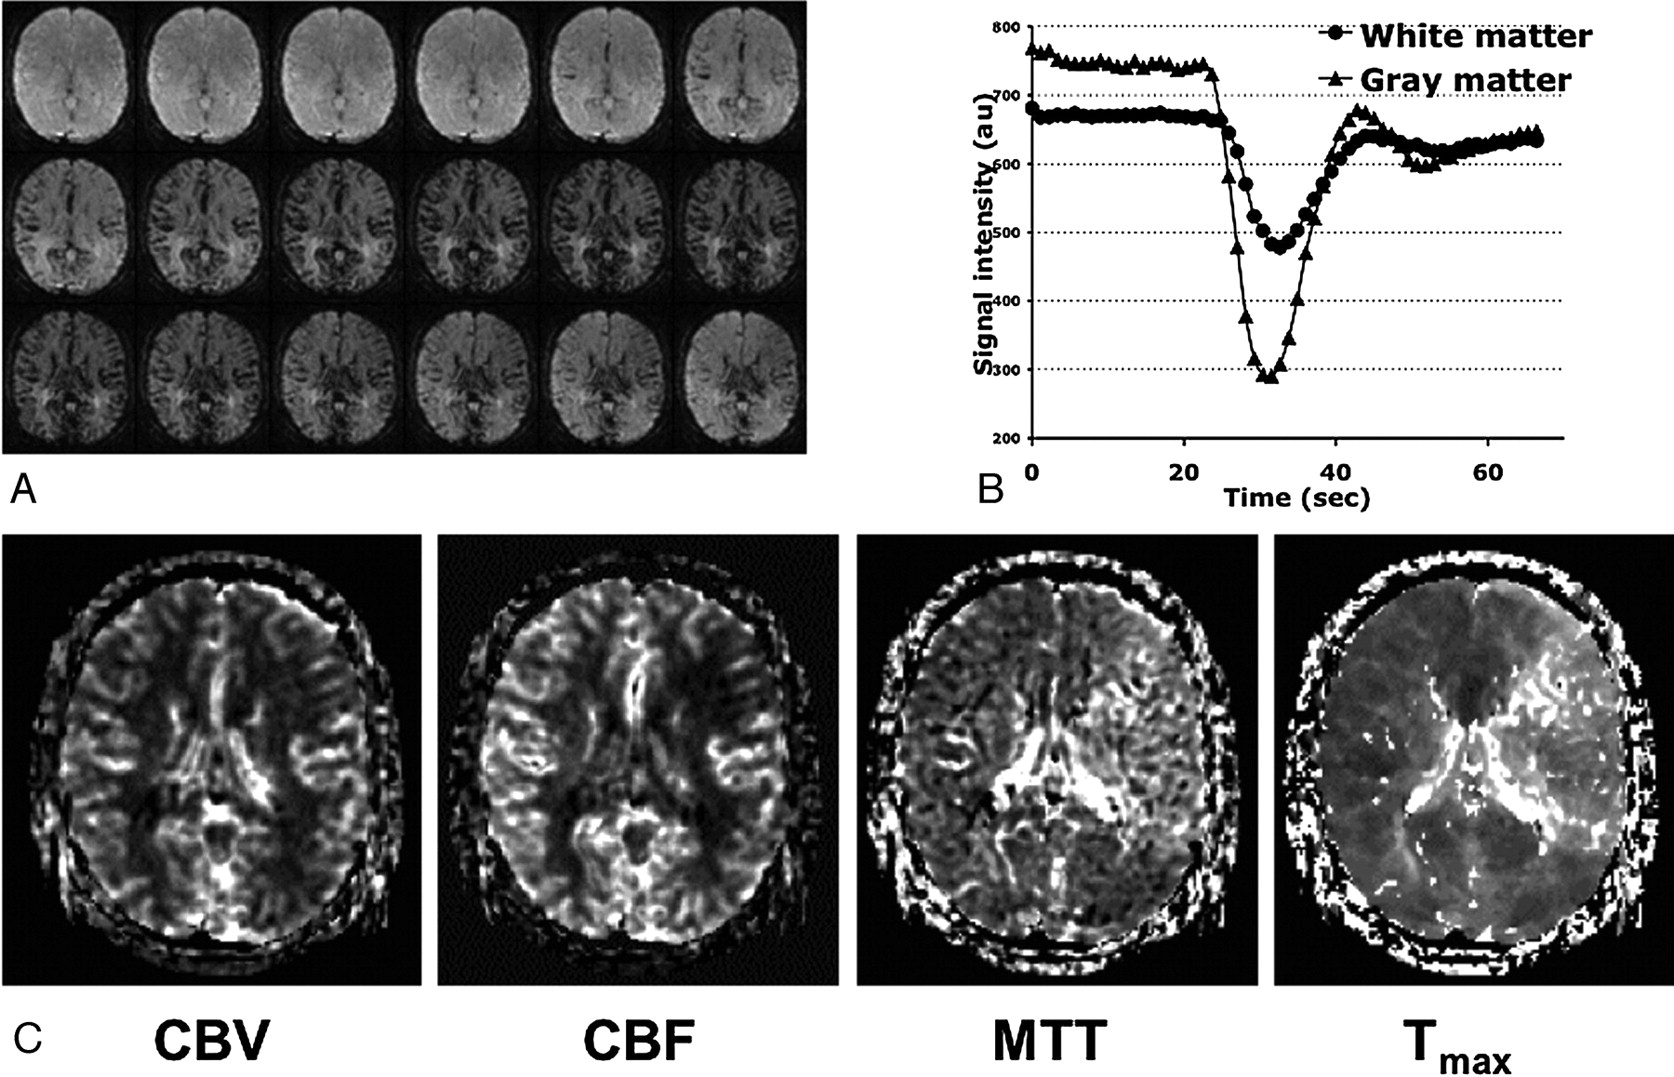

These agents can be used in a different way, as “tracers,” by injecting them as tight intravenous (IV) boluses and then imaging their initial passage through the brain vasculature. This requires larger gauge IV catheters and higher injection rates (≥4 mL/s), coupled with repeated rapid cine imaging of a volume of interest while the contrast passes through the capillary network. To record the tracer concentration during this passage faithfully, one must acquire images at a rate faster than the time it takes the bolus to pass through the tissue, which is usually on the order of several seconds. This acquisition requires rapid imaging sequences such as Cartesian or spiral echo-planar imaging (EPI). Images are first acquired to determine the baseline signal intensity of each voxel. When the bolus passes through the voxel, the signal intensity drops (Fig 1). This drop occurs because the contrast agent is confined to the vascular space, which creates microscopic variation in the local magnetic field, which directly leads to decreased signal intensity on gradient-echo images. The intravascular contrast also creates magnetic field gradients around the vessel, which cause signal-intensity loss when protons diffuse in these gradients.1 One can quantify the change in transverse relaxivity (ΔR2 or ΔR2*, for spin-echo or gradient-echo, respectively) at each time point and in each voxel as 1) where S(t) is the signal intensity in the voxel at time t and S0 is the baseline signal intensity before the bolus arrives. This relaxivity change is assumed to be linearly proportional to the tissue contrast agent concentration (though this assumption has been questioned recently2) and confined within the intravascular space without leakage. It has been suggested that the effects of extravasation can be minimized with the application of a preloading dose of contrast agent3 or by using multiecho methods.4,5 More complex modeling has been undertaken to parse out the separate effects of permeability, and some of these methods are discussed in the section on permeability imaging.

A, Time course of the signal intensity from 1 section of a multisection gradient-echo EPI dataset at 1.5T during gadopentetate dimeglumine passage, TR/TE = 1,125/49 ms. During the first pass, signal intensity decreases due to the microscopic field-strength variations and water diffusion through gradients created by the intravascular contrast agent. B, Signal intensity versus time for regions of interest in the gray and white matter. C, From these curves and an estimate of the AIF, maps of perfusion-weighted parameters such as CBV, CBF, MTT, and Tmax can be created. Note the prolonged MTT and Tmax in the left hemisphere, representing ischemic tissue within the left middle cerebral artery territory. Sec indicates seconds; au, arbitrary units. Image courtesy of Dr. Rexford Newbould, Stanford University.